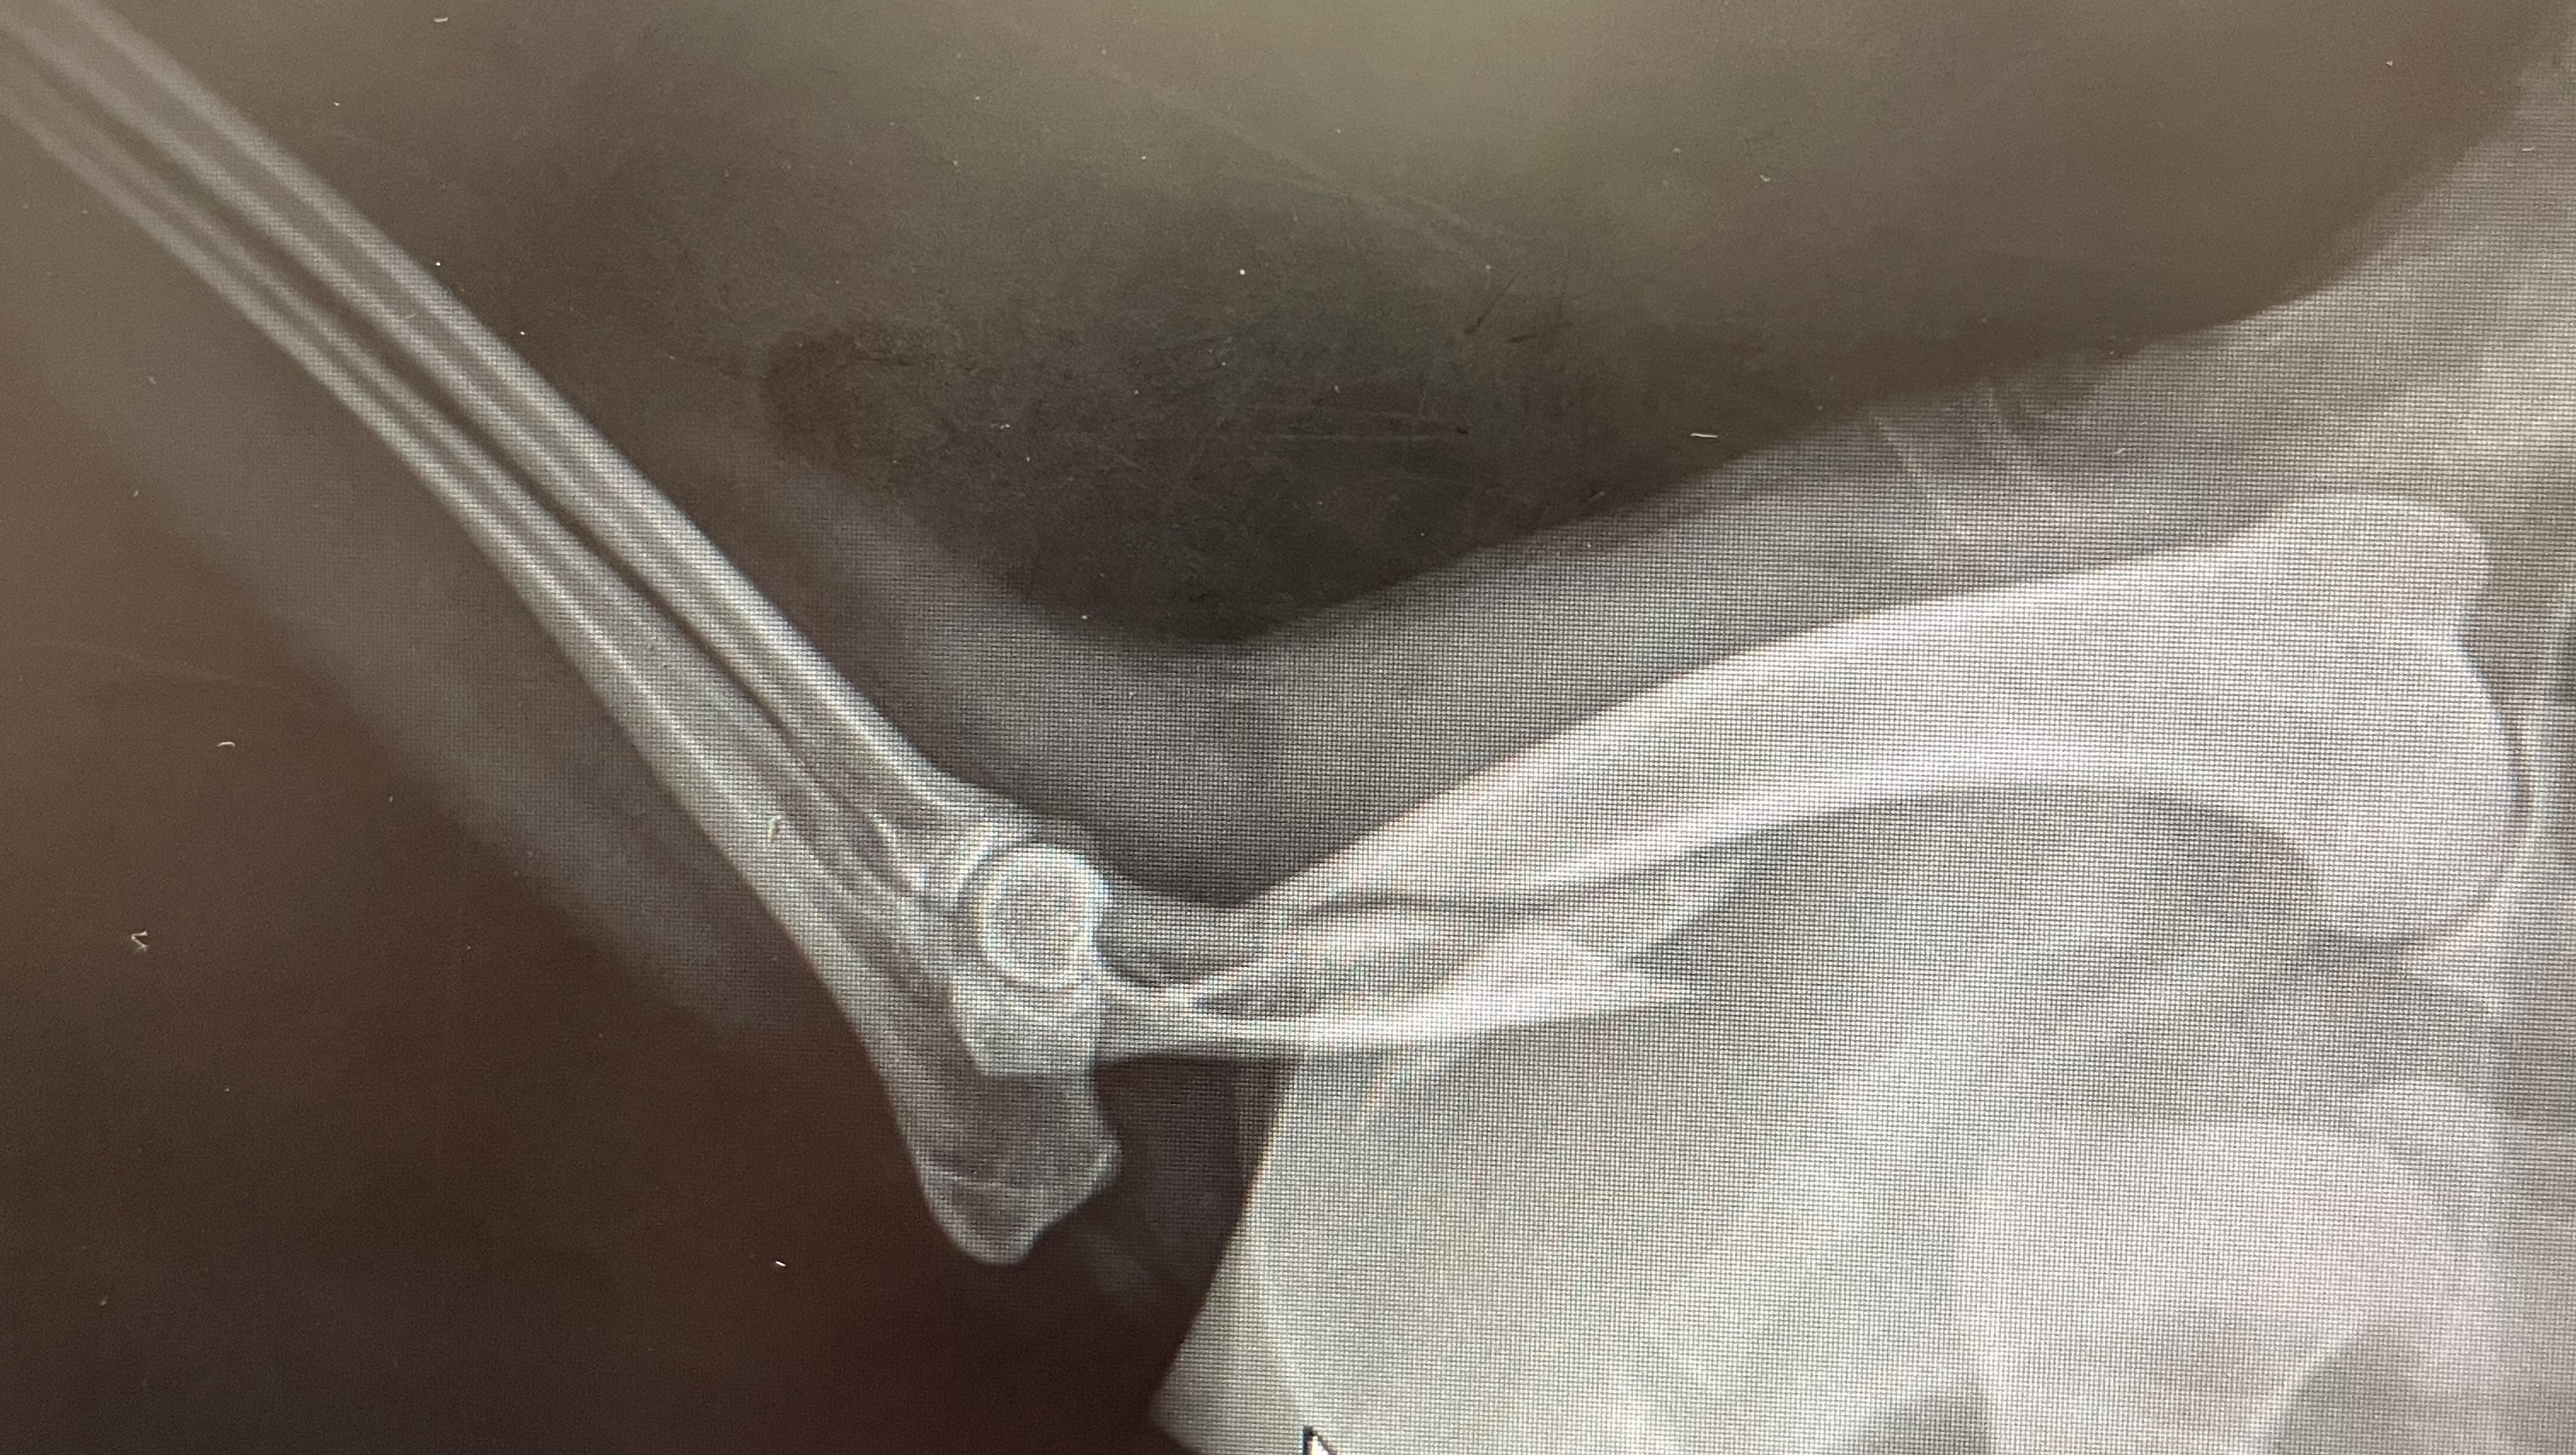

Hi, my name is Cydney Melton & my two dear friends’ dog Rascal got hit by a car July 20. Unfortunately with a dislocated back leg and a broken front leg, the surgeries will come out to $12,000. They would really appreciate the support to help pay these surgery bills, as it is a financial hardship on them and they need to help Rascal recover and get his surgeries. We would all really appreciate the help. Thank you.